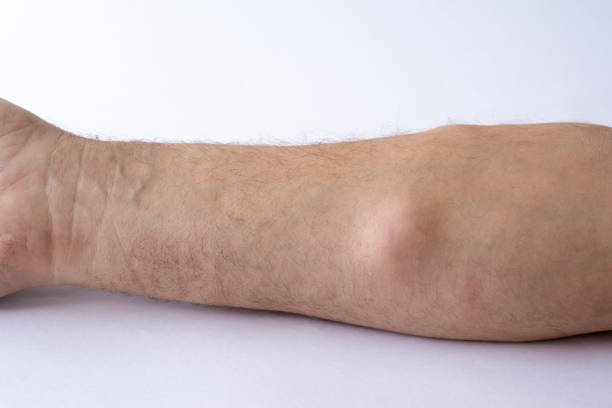

피부 아래 말랑한 혹은 혹이 발생하면, 이는 지방종의 가능성을 고려해야 합니다.

이러한 피부 이상은 혹의 형태로 나타나며, 말랑한 질감을 가지고 있습니다.

피부 아래 말랑한 혹: 지방종의 가능성?

말랑한 혹이 피부 밑에서 만져진다면, 이것은 지방종일 가능성이 높습니다. 지방종은 피부 아래 지방 세포들이 한데 모여 혹 형태로 나타나는 피부 질환입니다.

주로 팔에 다수의 작은 혹이 나타나는 경우, 다발성 지방종을 의심할 수 있습니다.